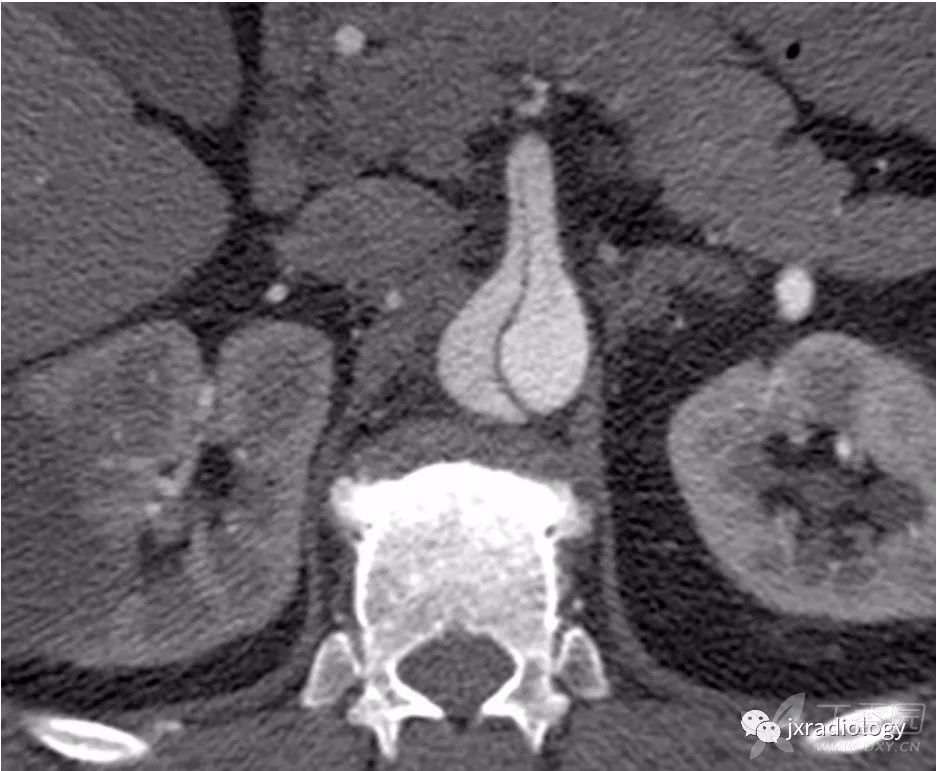

内膜内套叠是一种环状的主动脉夹层,类似于风向袋( 图10 )。在这些情况下,内膜撕裂通常位于冠状动脉开口附近,通常内腔是真腔。

图10:增强CT显示内膜套叠。

一种特殊类型的主动脉夹层,主动脉壁内膜呈圆形分离。内腔是真腔(星号)。